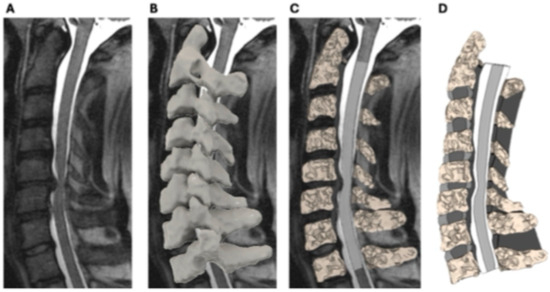

2.1. Generation of Patient-Specific Surface Model from MRI

2.2. Finite Element Modeling of Cervical Spine